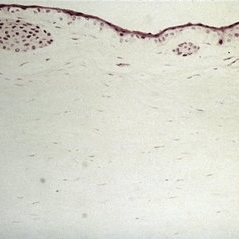

Slide 7-9

Feb 25 2019 by Lancaster Course in Ophthalmology

Subepithelial bullae in ocular pemphigoid.

Condition/keywords: subepithelial bullae